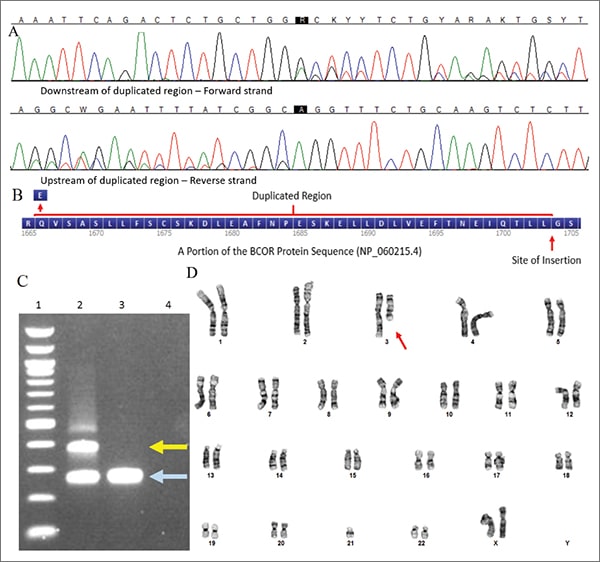

As a diagnosis of HGNET was suspected, Sanger sequencing of exon 15 of the BCOR gene was performed on DNA isolated from fresh frozen tumor tissue. An in-frame internal tandem duplication in exon 15 of the BCOR gene, c.4997_5110dup (p.Leu1703_Gly1704ins38), was detected (Fig. 2A–C). Additional testing included microarray analysis, which showed loss of the entire chromosome 3 long arm, and chromosome analysis (Fig. 2D), which showed an unbalanced translocation involving chromosome 3 and 21 with loss of 3q (46,XX,der(3;21)(q10;q10)[6]; 46,XX[14]). This karyotypic abnormality was not a known recurrent aberration associated with any particular tumor type. Additional reference laboratory testing showed the tumor cells had strong diffuse nuclear immunoreactivity for BCOR. BCOR rearrangement was not detected by fluorescence in situ hybridization testing. However, approximately three percent of the nuclei showed three BCOR signals, consistent with a duplication.

Methods. Routine H&E stains and immunohistochemical stains at our institution were performed on 4-µm thick sections from formalin-fixed, paraffin-embedded tissue. DNA was isolated from fresh frozen tissue (tumor cells estimated to be greater than 50 percent of specimen via examination of an adjacent section) per manufacturer’s instructions using a Maxwell Rapid Sample Concentrator instrument and tissue extraction kit (Promega, Madison, Wis.). Purified DNA was subjected to PCR, then bidirectional Sanger sequencing (BigDye Terminator v3.1 Cycle Sequencing Kit and Applied Biosystems 3500 Genetic Analyzer, Thermo Fisher Scientific, Waltham, Mass.) using primers targeting BCOR exon 15 with sequences as previously described.4 Generated sequences were aligned to reference sequence NM_017745.5 and analyzed using Sequencher software (v.5.4.6, GeneCodes, Ann Arbor, Mich.). Other regions of the gene or genome were not sequenced. Variants found were interpreted for clinical significance per the AMP/ASCO/CAP guidelines for somatic variant interpretation.11

Of note, the variant reported above is described per Human Genome Variation Society (HGVS) guidelines. It corresponds to the one reported by Yoshida, et al., and Roy, et al., as: c.5099_5212dup (p.Leu1737_Gly1738ins38) using BCOR reference transcript NM_001123385.1.3,12 References to BCOR exon 16 also exist in the research literature due to use of custom exon numbering; this exon corresponds to exon 15 above (systematic numbering approach).